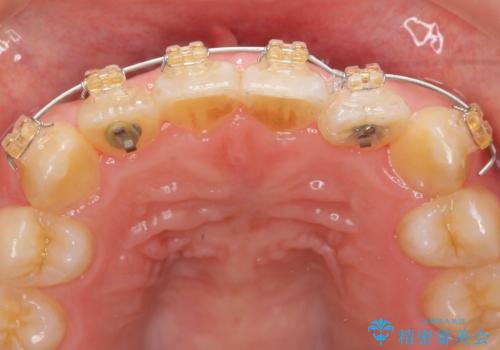

マウスピース矯正では改善の難しい前歯のねじれを前歯の部分ワイヤー矯正で改善したのち、インビザライン矯正を行い歯列を整えます。

インビザラインを行う前に前歯の部分矯正を行ったことで、しっかりとねじれが取れ整った歯列へと仕上げることが出来ました。